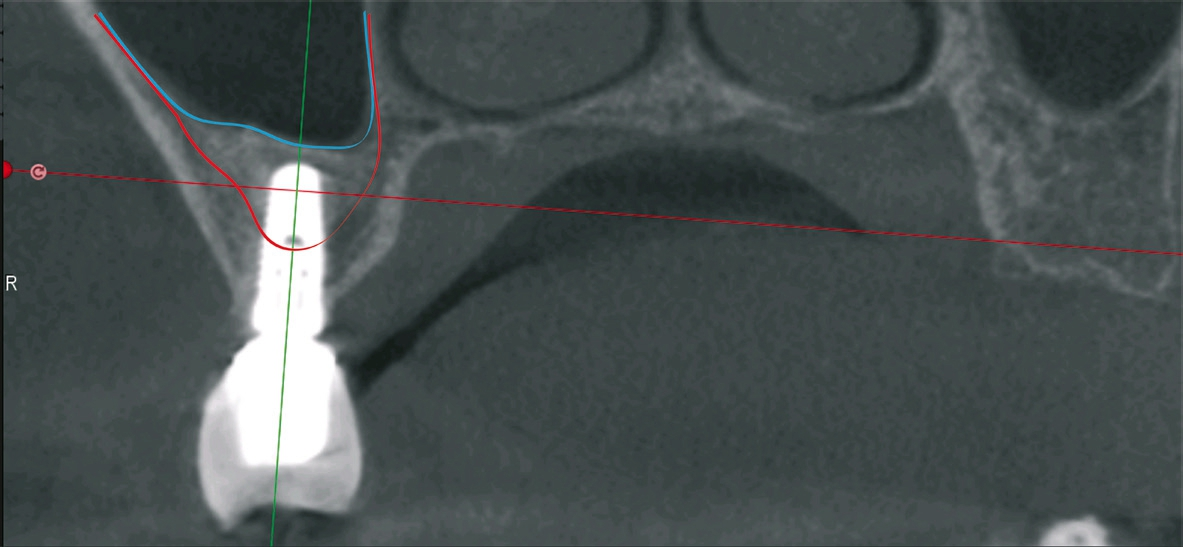

Das System beruht auf der Schaffung einer Druckkammer, in der der Ersteintritt durch den knöchernen Kieferhöhlenboden bei etwa 1,2 bis etwa 1,5 bar unter Zuhilfenahme eines speziellen Bohrers ? der Jederfräse ? in der Druckkammer stattfindet, ohne dass eine Berührung der Kieferhöhlenschleimhaut stattfindet. Der Schutz der Kieferhöhlenschleimhaut erfolgt durch die mit hohem Druck ausgestattete und pulsierende Wassersäule, die bei kleinster Eröffnung des knöchernen Kieferhöhlenbodens dazu führt, dass die Schneider‘sche Membran nach kranial eleviert wird (Abb. 2). Die Darstellung des Druckaufbaus und Verlaufes erfolgt mikroprozessorgesteuert auf einem Bildschirm der Pumpeneinheit in Echtzeit. Der Anwender sollte im Moment des Druckabfalles den Vortrieb der Fräse unterbrechen (Abb. 3). Die Elevation der Schleimhaut erfolgt nun weiterhin mikroprozessor-überwacht und auf dem Monitor kontrolliert in 0,2 ml Schritten fraktioniert, bis das gewünschte Augmentationsvolumen erreicht worden ist. Dies ermöglicht auch während der Elevation eine sichere Beurteilung, ob die Schleimhaut eine Perforation aufweist. Zum Lösen der Membran wird häufig ein Druck in der Größenordnung von 0,4 bis 0,6 bar beobachtet. Im Zustand der elevierten Membran sollte die Erweiterung der meist nur Stecknadelspitzen bis Stecknadelkopf großen Perforation unter Zuhilfenahme eines kugelförmigen, fein diamantierten, rotierenden Instrumentes erfolgen, um ein leichteres Einbringen des Augmentationsmateriales zu ermöglichen (Abb. 4). Darauffolgend wird die in der Kieferhöhle und sich unter der Schneider‘schen Membran befindliche Kochsalzlösung mit dem Jeder-System abgepumpt und optisch auf Lufteinschlüsse kontrolliert. Für den seltenen Fall einer Schleimhautperforation wird dann die Anwendung der klassischen Tatum-Technik mit lateralem Fenster empfohlen, die eine subsidiäre Versorgung der Perforation zum Beispiel mit einer Kollagenmembran unter direkter Sicht ermöglicht. In allen anderen Fällen folgt die Augmentation mit einem Knochenersatzmaterial der Wahl. Nach den aktuellen Übersichtsarbeiten scheint das Augmentationsmaterial in der Kieferhöhle keinen signifikanten Einfluss auf das Implantatüberleben zu nehmen [15].

Patient 1: männlich, 50 Jahre alt, Anamnese: unauffällig; Diagnose: Schaltlücke. Knochenersatzmaterial: Geistlich Bio- Oss® (Geistlich Biomaterials) (Abb. 5 bis 10).